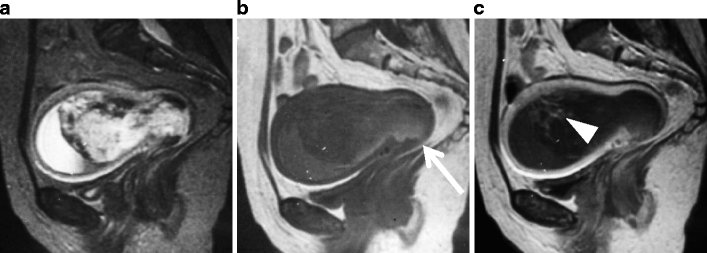

Undifferentiated Endometrial Sarcoma

Undifferentiated stromal sarcoma in a 22-year-old female who presented with acute abdomen due to uterine rupture. a Sagittal T2-weighted image demonstrates an ill-defined myometrial mass of heterogeneous appearance in the anterior wall (arrows). The upper portion of the tumor containing fluid-fluid level represents hemorrhagic necrosis within the tumor (arrowheads). b T1-weighted image demonstrates increased signal intensity corresponding to the area of hemorrhagic necrosis (arrowheads). Hemorrhagic ascites of increased signal intensity also is present in the Douglas fossa and uterovesical fossa (asterisks). c Postcontrast T1-weighted image with fat suppression demonstrates heterogeneous enhancement within the solid component of the tumor (arrows)